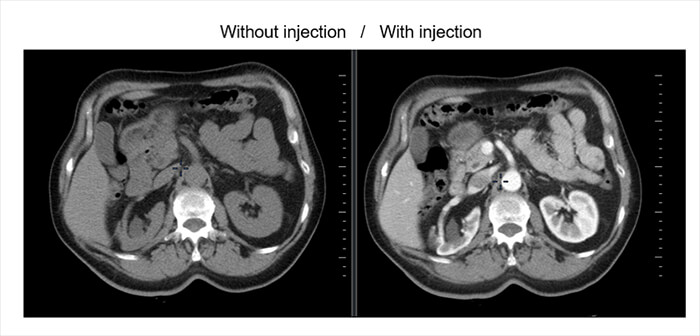

Contrast Injections

The purpose of contrast-enhanced CT (CECT) is to find pathology by enhancing the contrast between a lesion and the normal surrounding structures.

In the Left image (without contrast injection): organs present similar grayscale preventing proper differentiation of tissues.

The right image shows the contrast agent highlights the different vessels, defines tissues and thus indicates to the radiologist the behavior of the different organs.

Different Image Phases

Non-enhanced CT helps detect calcifications, fat in tumors, fat-stranding as seen in inflammation like appendicitis, diverticulitis, omental infarction, etc.

The arterial phase is 15-20 sec after bolus tracking. All structures that get their blood supply from the arteries will show optimal enhancement. Hepatic or late portal phase: 50-60 sec after the bolus. Although the hepatic phase is the most accurate term, most people use the term “late portal phase”.

In this phase, the liver parenchyma enhances through the blood supply by the portal vein and you should see already some enhancement of the hepatic veins. The delayed phase is usually 6-10 minutes after the bolus. Sometimes called “washout phase” or “equilibrium phase”. There is wash out of a contrast in all abdominal structures except for fibrotic tissue because fibrotic tissue has a poor late washout and will become relatively dense compared to normal tissue.